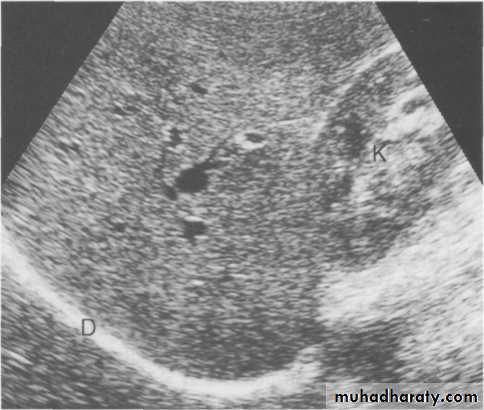

Radiological examination of the liver

Ultrasound of the liver.Ultrasound of normal liver. Longitudinal scan showing uniform echo pattern interspersed with bright echoes of portal triads and echo-free areas of hepatic and portal veins. D, diaphragm; K, right kidney